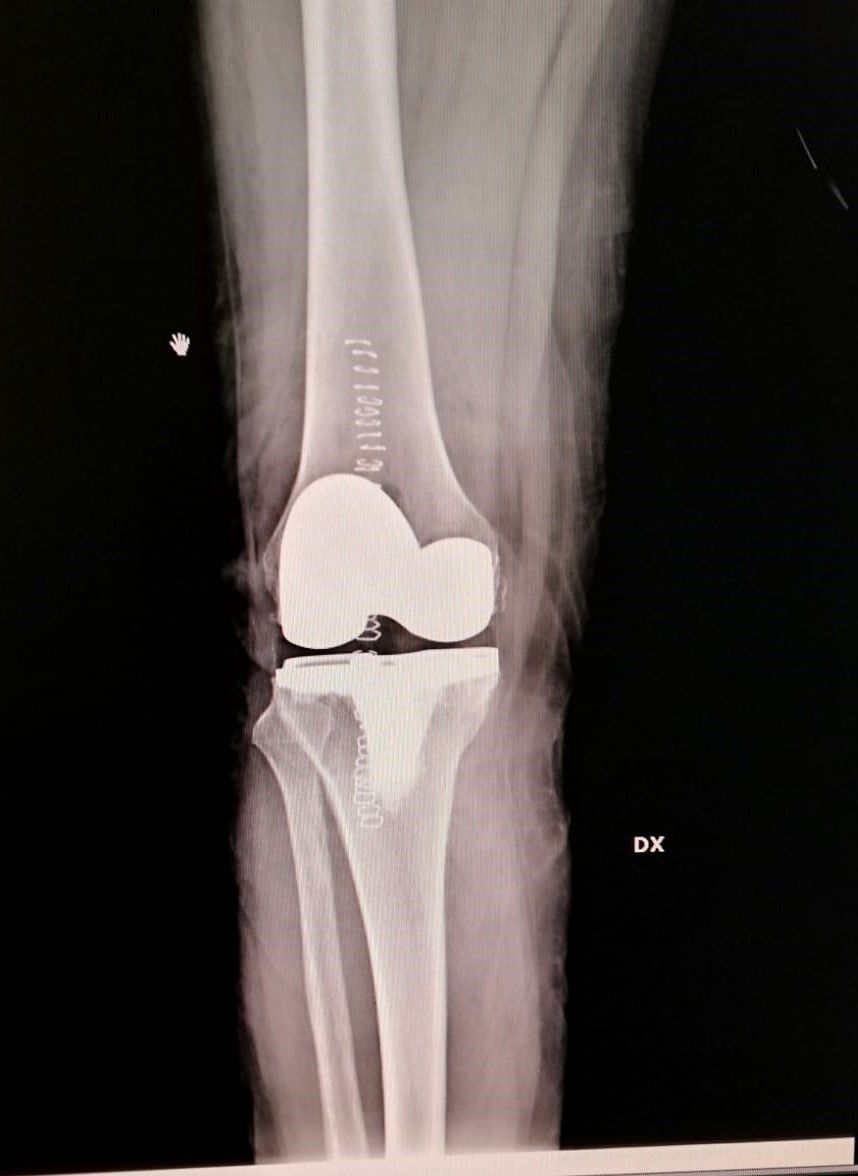

- protesi totale di ginocchio

- protesi mono-compartimentale del ginocchio